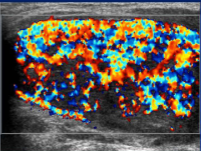

Which statement about the sonographic appearance of Hashimoto’s thyroiditis is TRUE?

It shows hypoechoic micronodules with echogenic septations, creating a pseudonodular or “giraffe” pattern, and Doppler may show normal, decreased, or occasionally increased flow.

This pseudo-micronodular appearance of the thyroid is characteristic of:

Hashimoto’s thyroiditis